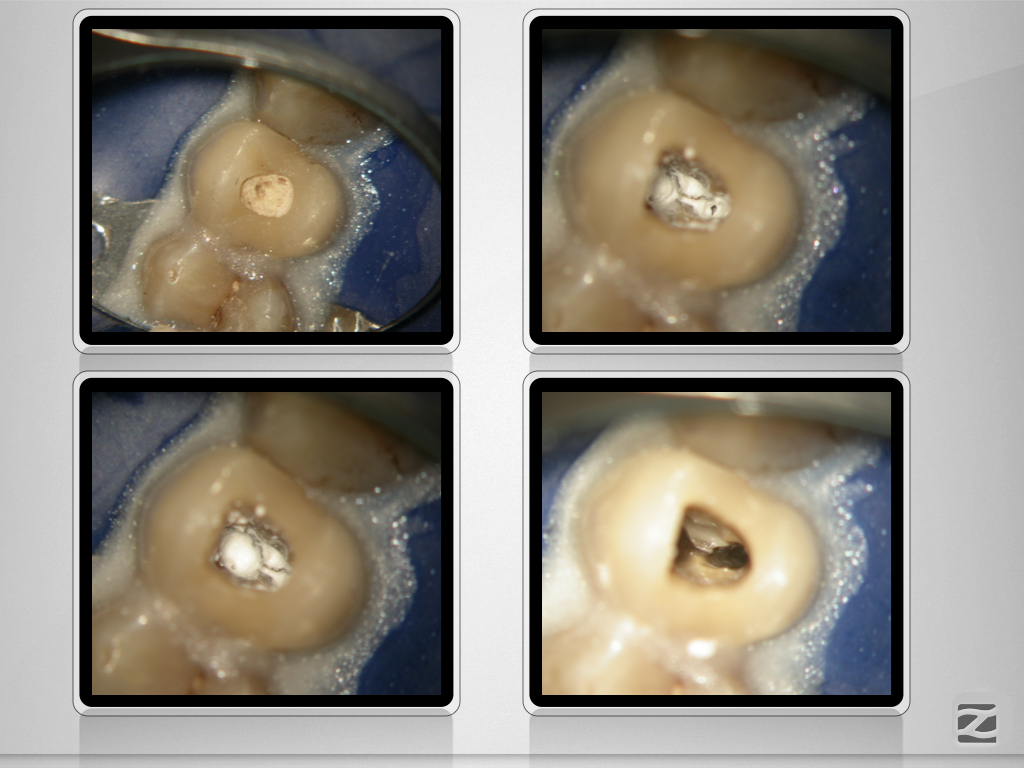

24D.005

Enger Dreier